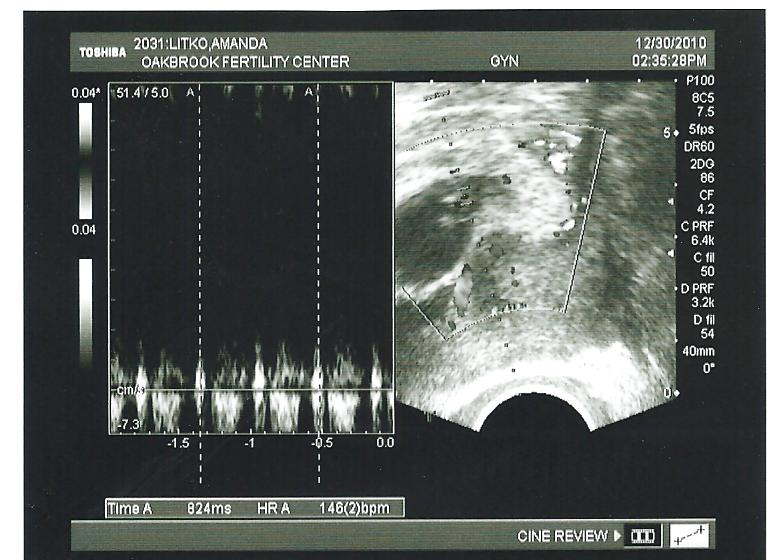

From babymasi.blogspot.com

Baby Masi Our Growth Ultrasound What Is A Growth Check Ultrasound growth scans are a common pregnancy ultrasound scan. an ultrasound scan can be used for screening to look for abnormalities in the physical structure of the baby, for. a growth scan, also known as a fetal growth ultrasound or simply a growth ultrasound, is a specialized imaging. a growth scan is important to confirm the normal. What Is A Growth Check Ultrasound.